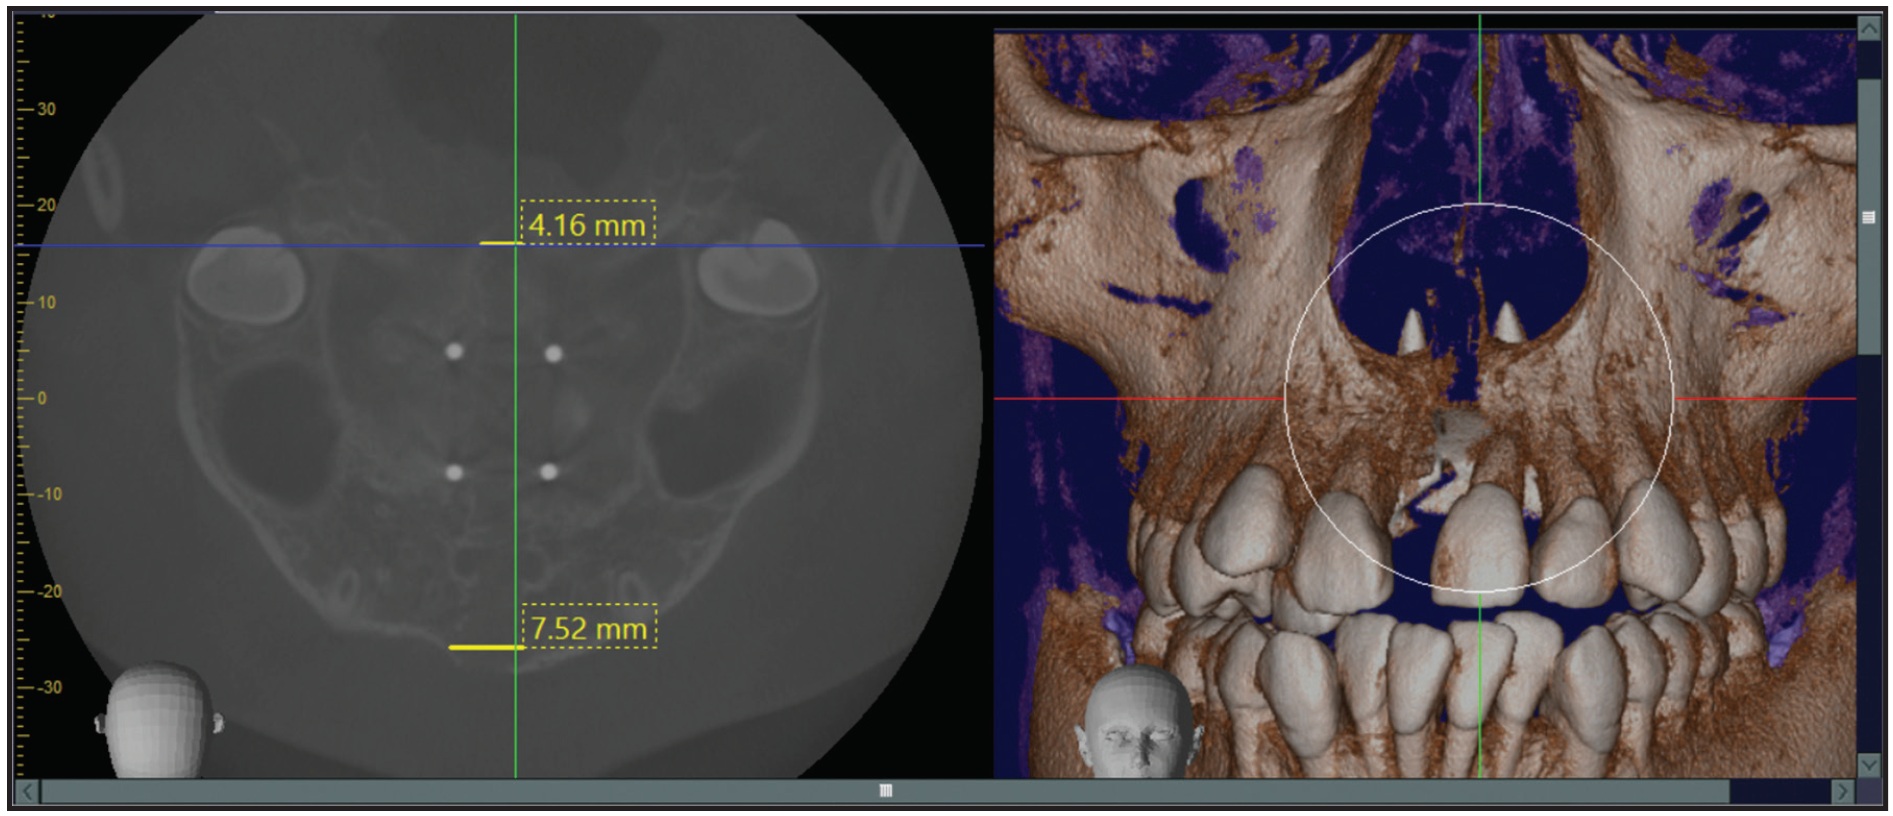

One week later, a progress CBCT confirmed 7.52mm of widening in the anterior part of the suture and 4.16mm in the posterior part (Fig. 6).

Fig. 6 Midpalatal suture expansion.